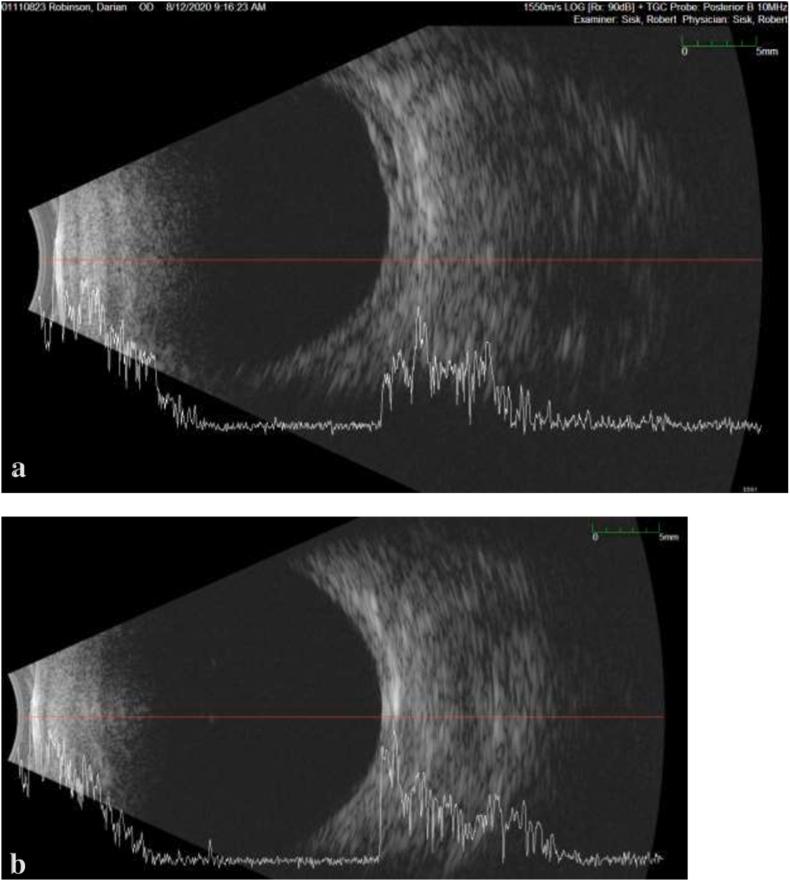

A 17-year-old male with pathologic myopia and history of retinopathy of prematurity previously treated with laser ablation in both eyes presented with reduced visual acuity in his right eye from choroidal detachment and hypotony maculopathy. In the absence of uveitis and intraocular pressure lowering medications, it was determined that repeated nocturnal ocular compression from circumaural headphones created episodes of hypotony. With avoidance of this behavior and in the absence of pathologic aqueous dynamics, intraocular pressure normalized with gradual resolution of choroidal thickening and restoration to baseline visual acuity.

Persistent and prolonged ocular compression, even unintentionally, can create hypotony with risk for vision loss, maculopathy, and choroidal detachment.